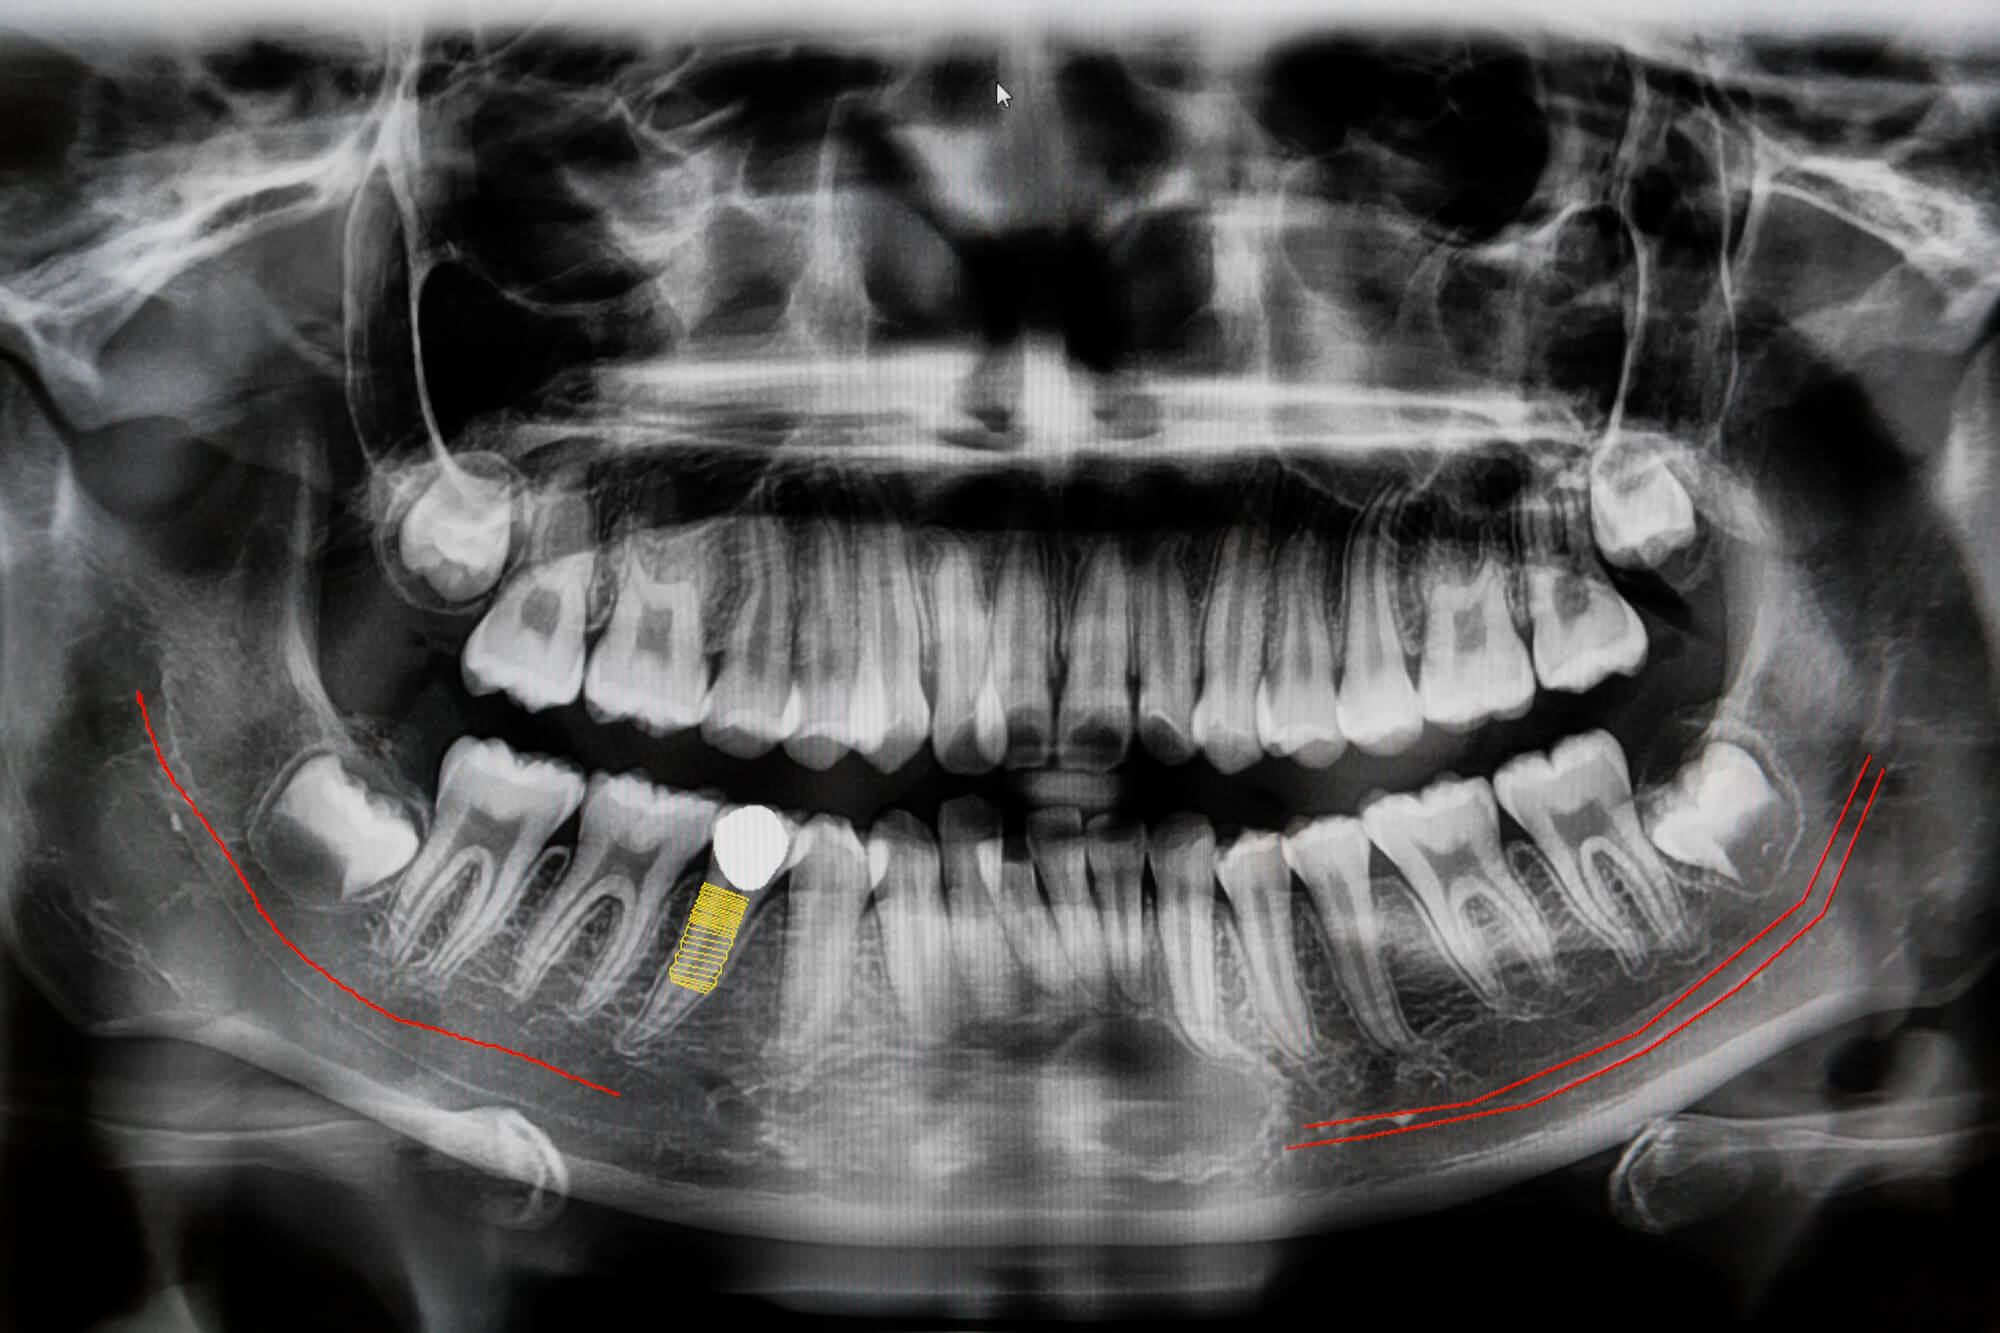

Loose implants indicate a serious problem. If the restoration appears unsteady, it could be due to either bone loss or an infection in the implant site, known as peri-implantitis. It may also happen if the implant does not fully integrate with the bone during the healing process.

Loose implants must be addressed promptly, though, as an infection near your bone can be very dangerous. Make an appointment with your dentist right away. In the meantime, refrain from biting the side of your implant that feels loose.

Avoid repairing it yourself, as this may result in additional harm. A better result can be achieved with early intervention, which may include tightening the implant or treating any underlying problems.

This can easily lead to implant failure, requiring the removal of the implant. In fact, according to the American Academy of Implant Dentistry, 5–10% of dental implants may fail due to infection or incorrect healing. Afterward, conducting a bone graft is often necessary before considering inserting another implant.

Moreover, if bacteria infiltrate the implant site, they can cause an infection that spreads into the surrounding bone and soft tissue. If left untreated, peri-implantitis can lead to significant bone deterioration, compromising not only the implant but also adjacent teeth and overall oral health.